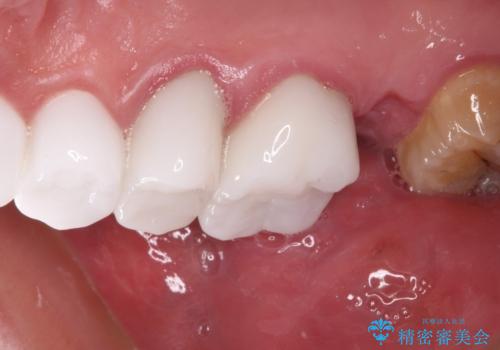

咬み合わせを改善するに当たって、抜歯しなければならない歯や歯列の改善が必要な箇所があったため、矯正治療やインプラント治療から始めていくこととしました。

不自然なくらい真っ白にしたいとのことでしたので、透明感のないフルジルコニアクラウンを用いて補綴することとしました。

本来、あまりにも不自然な歯となるため、フルジルコニアクラウンを前歯に使用することは、咬合力が強すぎる場合を除き、ほとんどありません。

それでも、色調、形態ともに不自然なくらい真っ白な歯をご希望でしたので、患者様には大変満足していただきました。